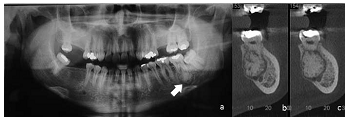

Odontologia » Cistos e Tumores , Patologia oral e Maxilofacial

Homem de vinte e cinco anos de idade, melanoderma, compareceu a unidade odontológica para a remoção de terceiro molar superior. Por imagem radiográfica, constatou-se aumento de volume radiopaco fundido ao ápice do dente 37 circundado por um fino halo radiolúcido, conforme indicado pela seta na imagem radiográfica a. Foi solicitada a realização de tomografia, para confirmação das características previamente identificadas. As imagens da tomografia correspondem às indicadas pelas letras b e c.

Considerando-se o aspecto patognomônico da lesão, é correto afirmar que se trata de